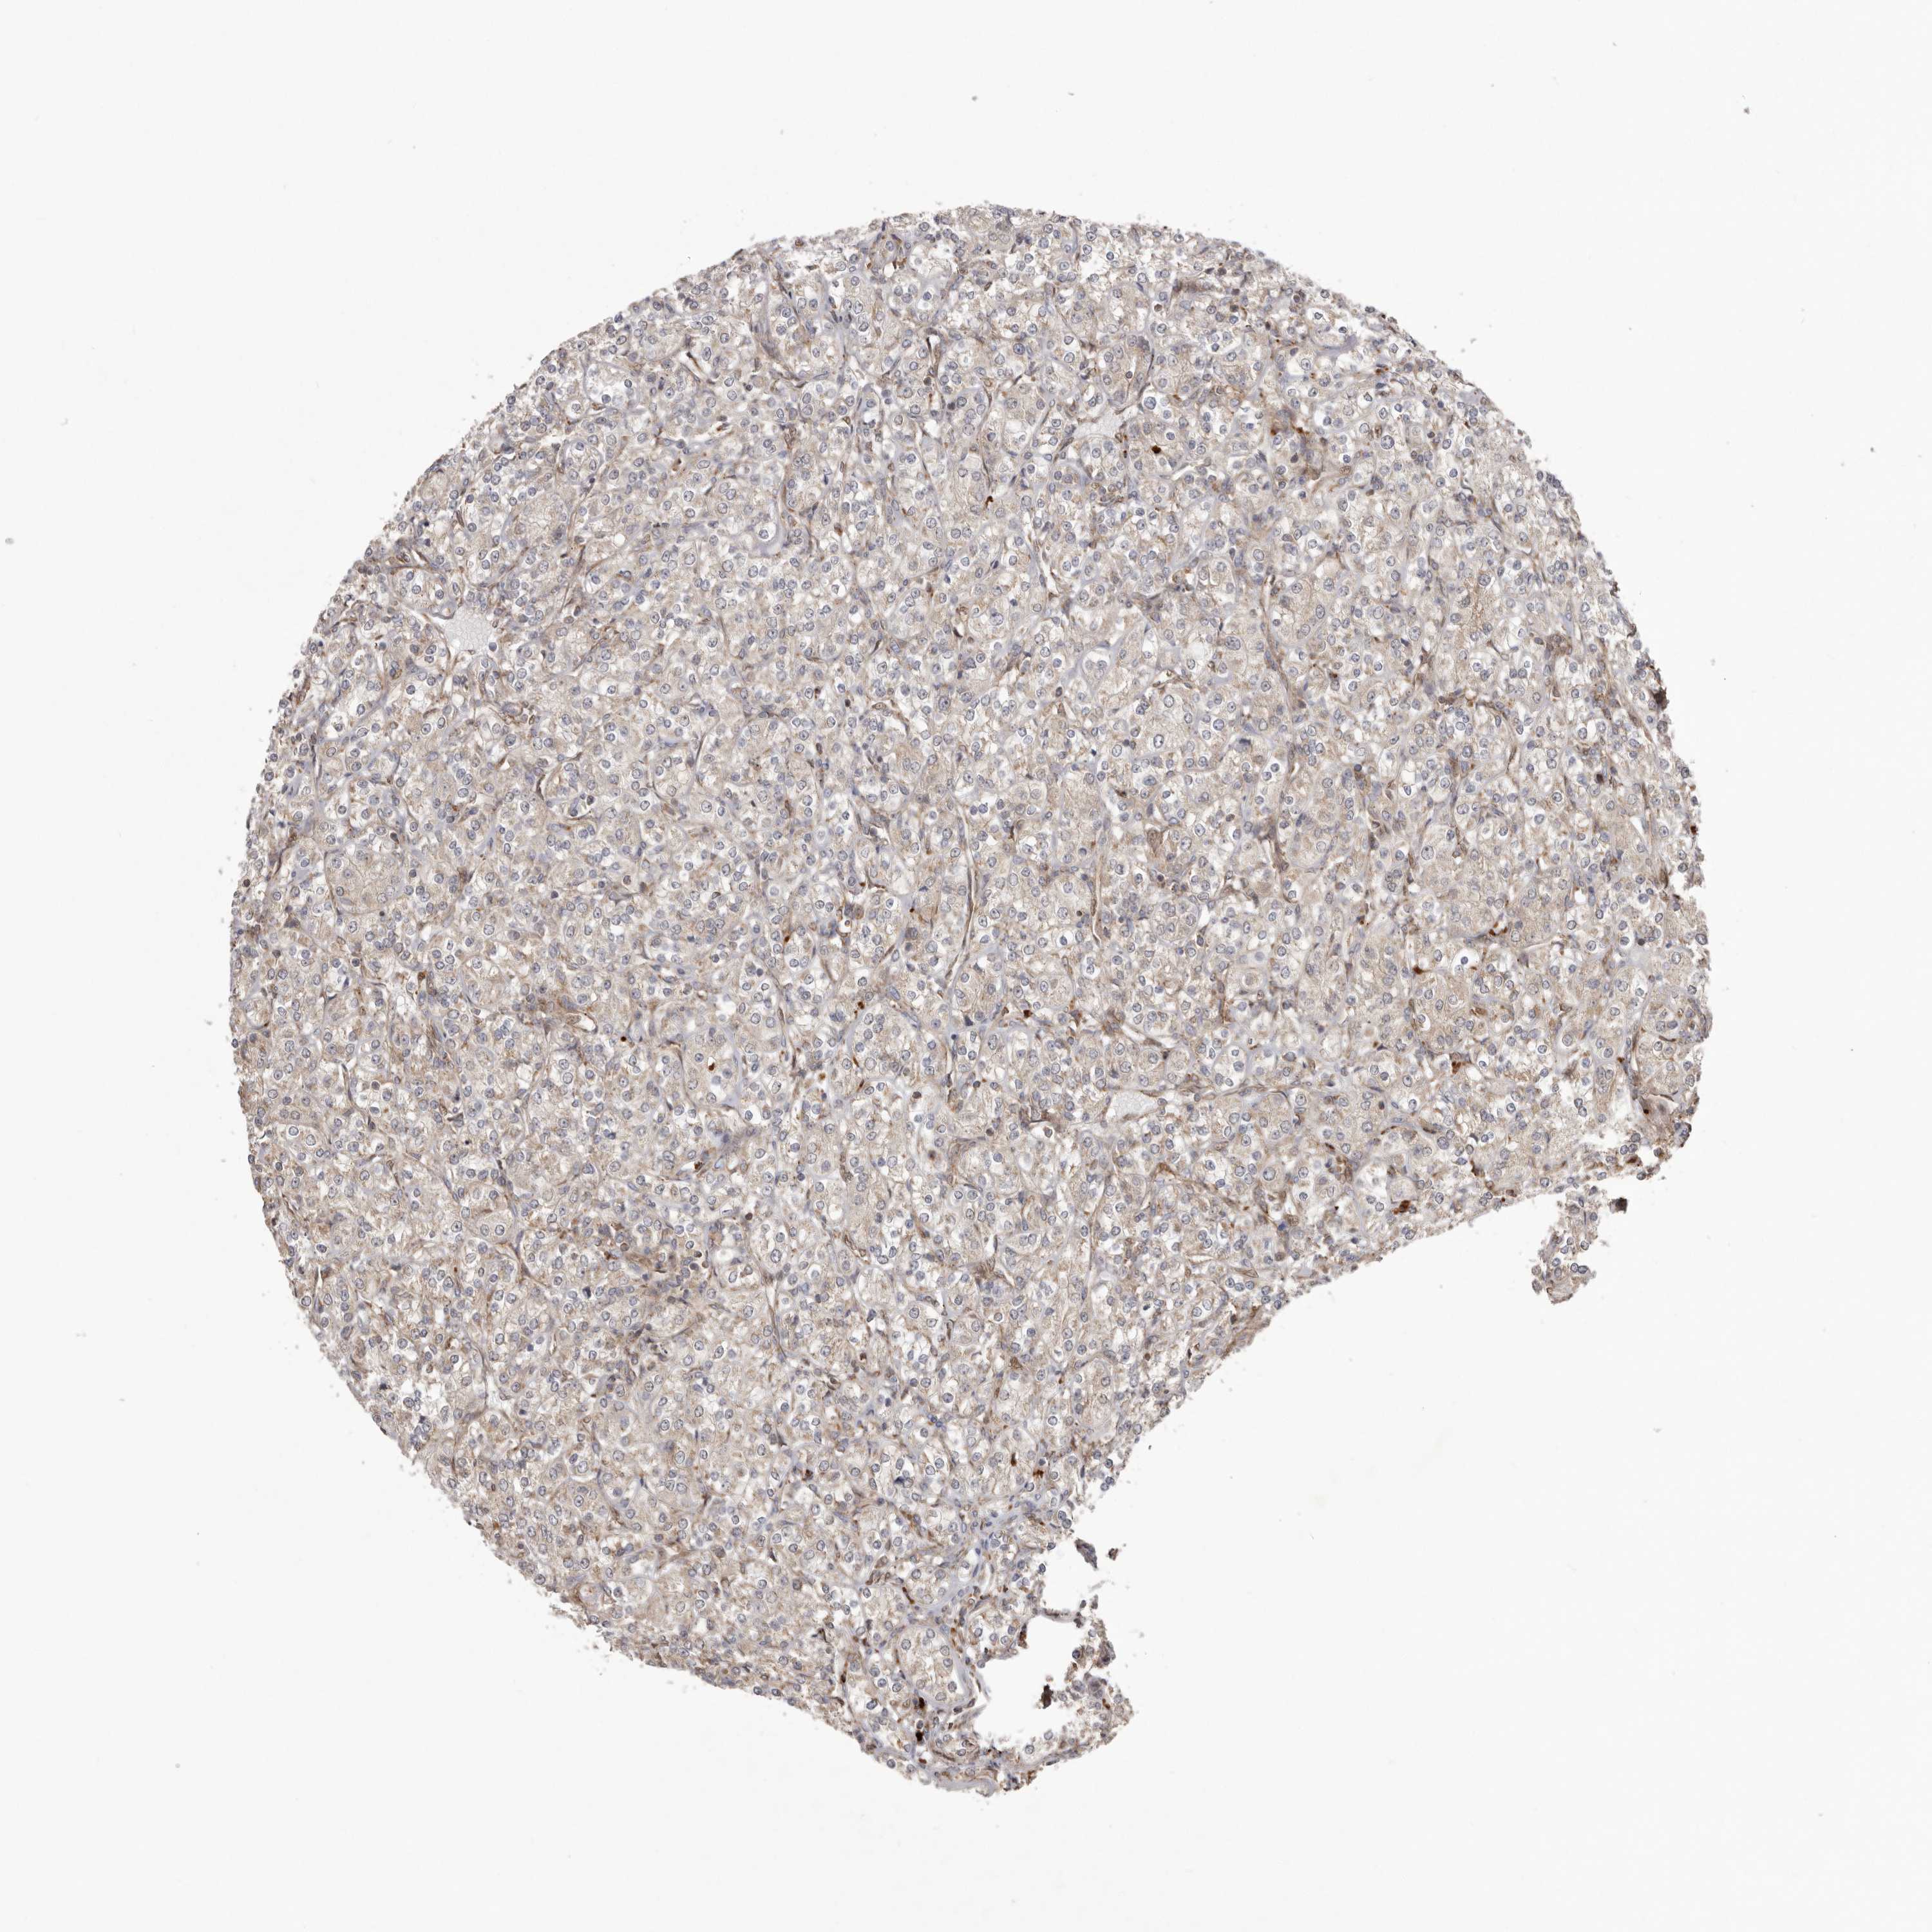

CANCER RENAL CANCER Show tissue menu

KICH TCGA KIRC TCGA KIRC VALIDATION KIRP TCGA PROTEIN RCC CPTAC PROTEIN EXPRESSION